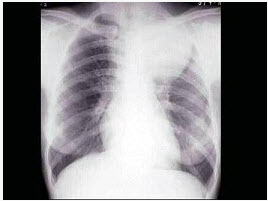

女,25岁,胸背痛半月余,胸片如图,最可能的诊断为()

A . 左上肺不张

B . 左上肺炎

C . 纵隔肿瘤

D . 左上肺癌

E . 左上肺炎性假瘤